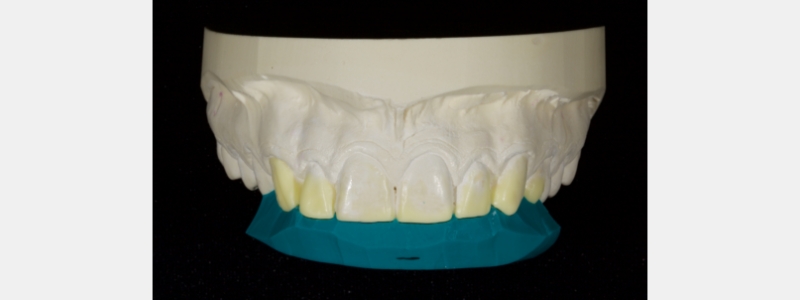

Usually, the composite resin is layered using a polyvinyl siloxane (PVS) palatal stent. Layering allows accurate control from palatal to facial, reducing the need for significant post-op occlusal adjustment.

I prefer a PVS putty, which is high contrast in color. For example, blue, green, or purple rather than beige or pink. PVS putty improves visualization when placing the initial composite shell.

When fabricating the stent, it will often extend onto the facial surface, resulting in access issues when layering. Instead, trim the stent with a sharp blade such as an 11 scalpel or a simple carpet knife. The trim should be through the incisal edge midway between the facial and palatal surfaces. The trim angle should mirror the tooth’s incisal-facial surface to be restored.